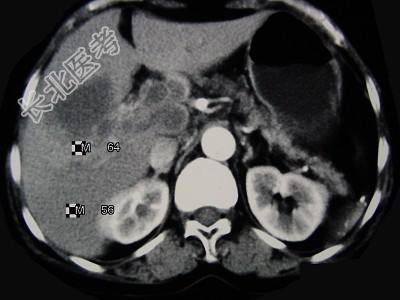

- 单项选择题女,65岁, 右季肋区疼痛二个月,CT扫描所见如图, 最可能的诊断为( )